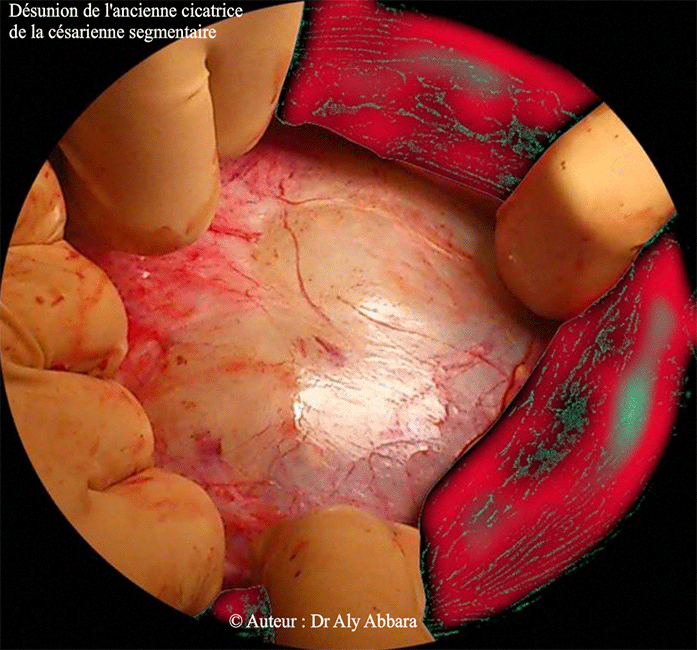

Images mettant en évidence une désunion totale d'une ancienne cicatrice de césarienne segmentaire transversale.

On observe sur cette image l'écartement important des deux berges de l'ancienne hystérotomie de la césarienne, avec seulement la berge supérieure individualisable, car la berge inférieure est rétractée derrière la paroi postérieure de la vessie.

Cette désunion totale de la cicatrice de l'hystérotomie permet d'apercevoir les membranes amniotiques recouvertes par le péritoine viscéral ; puis par transparence on identifie le liquide amniotique, les flocons du vernis et la présentation céphalique fœtale (vision directe per-opératoire).

Il s'agit d'une désunion cicatricielle survenant chez une patiente ayant dans ses antécédents deux césariennes segmentaires transversale.

Chez la patiente, cette pathologie qui pouvait être à l'origine de grave complications (rupture utérine et perte fœtale) était restée complètement asymptomatique, sa découverte fut fortuite lors d'une césarienne itérative, programmée, en dehors du travail, à 39 SA, pour utérus bicicatriciel.